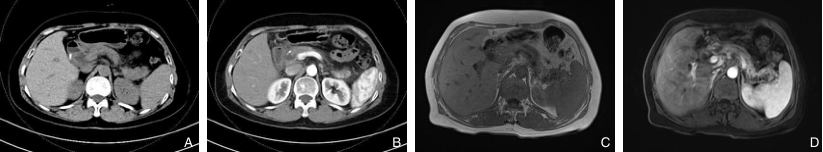

图1 术前影像学资料 A:术前CT平扫可见胰体尾部囊状扩张;B:术前CT增强可见胰腺体尾部可见多发小片状低密度灶,囊状扩张;C-D:术前MRI增强可见胰腺尾部呈多囊样改变,囊壁、分隔持续强化Fig.1